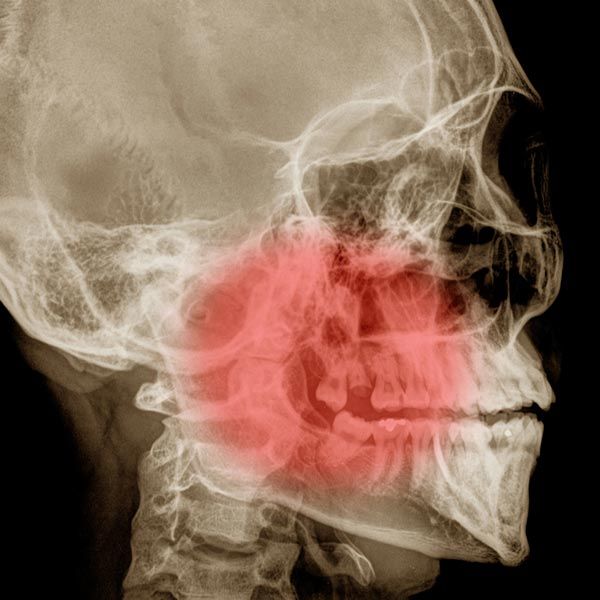

A comprehensive dental consultation at Han & Ahn can help you find out whether you suffer from a temporomandibular disorder. Our McLean practice uses cutting-edge digital x-ray and 3-D scanning dental technology to precisely diagnose temporomandibular disorders. Contact us if you are experiencing these symptoms, which are commonly related to unhealthy temporomandibular joints: